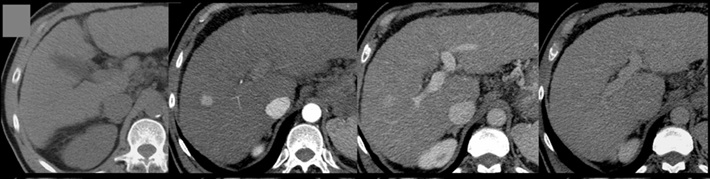

小肝癌的CT增强的典型表现

小HCC的动态增强CT的典型表现

CT小肝癌血流动力学类型

根据小肝癌血流动力学改变发现小肝癌改变仅占不到50%。根据动脉期增强病灶可发现约80-90%的病例

肝癌增强类型和肝癌的大小有关

小肝癌非典型增强类型可能包括以下: Low-high-low (典型表现)

iso-iso-iso (三期都为等密度)

high(hyper)-iso-iso (动脉期为高密度,门静脉期和平衡期为等密度)

high-high-low (动脉期和门静脉期为高密度,平衡期为低密度)

high-low-low (动脉期高密度,门静脉期和平衡期为低密度,典型的改变

low-low-low (动脉期-门静脉期-平衡期,都为低密度) 51-year-old woman with early hepatocellular carcinoma located in right hepatic lobe 三期均为低密度